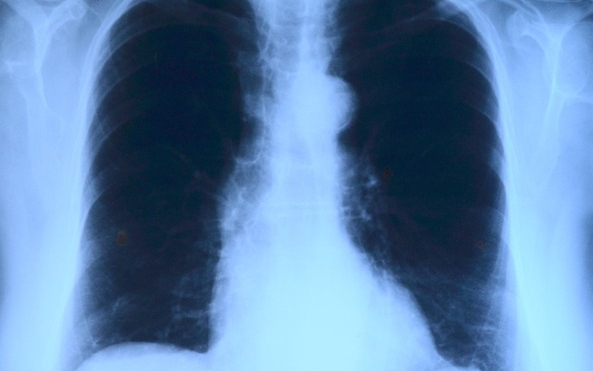

Elvégezték az országban az első tüdőverőér-tágítást

Az országban elsőként a Debreceni Egyetem Klinikai Központjában végeztek tüdőverőér-tágítást - közölte a felsőoktatási intézmény sajtóirodája kedden az MTI-vel.

A nemzetközi orvoscsoport múlt hét szombaton két betegnél hajtotta végre a beavatkozást, amellyel a tüdőerek magas vérnyomását csökkentették. Mindkét páciens krónikus thromboembóliás pulmonális hipetróniában szenvedett, amely súlyos nehézlégzést, kisebb fizikai terhelhetőséget és akár eszméletvesztést is okozhat. Az első hazai ballonos pullmonális értágítást (BPA) Irene Lang professzor, a bécsi Allgemeines Krankenhaus (AKH) kórház II. Belgyógyászat-Kardiológiai osztályának vezetője és tanítványa, Christian Gerges végezte a debreceni kardiológiai és szívsebészeti klinika intervenciós kardiológusainak közreműködésével - olvasható az egyetem közleményében.

A nagy szakértelmet és türelmet igénylő, komplex katéteres eljárást egy 59 éves férfinál és egy 82 éves nőnél végezték el. A 2-3 órás beavatkozás során a tüdő véráramlását akadályozó vérrögöket ballonnal kitágították, így az áramlási akadály mérséklődött, a tüdőerekben pedig csökkent a nyomás, ezzel együtt a szív terhelése is.